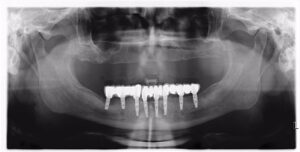

Full-Mouth Dental Implant Solutions in Rajkot

If you’ve lost most or all of your teeth, our full-mouth dental implant solutions in Rajkot can give you back a strong, beautiful smile.

- All-on-4 and All-on-6 implants

- Full-arch fixed hybrid dentures

- Zygomatic implants (for patients with low bone volume)

Every plan is customized based on jawbone analysis, ensuring comfort and durability